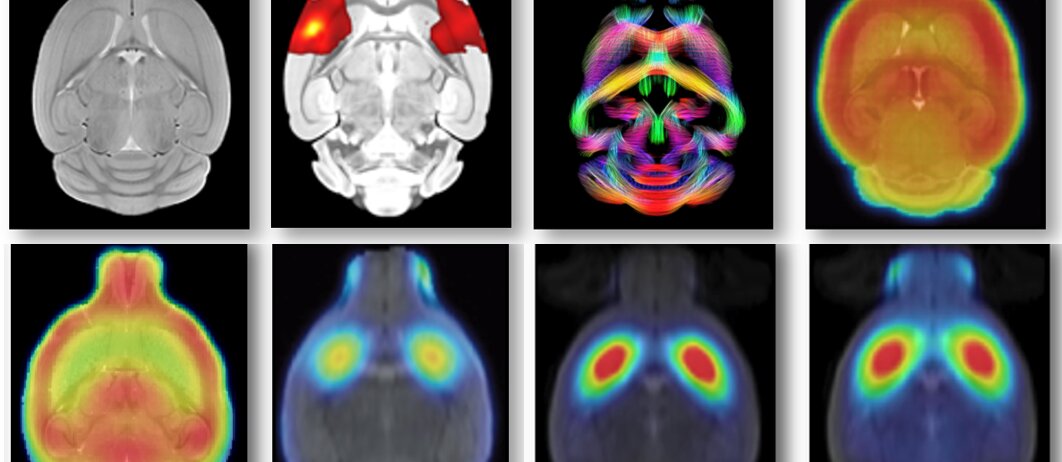

Early multimodal biomarker imaging: MRI and PET

PET AWAKE imaging for moving and interacting animals